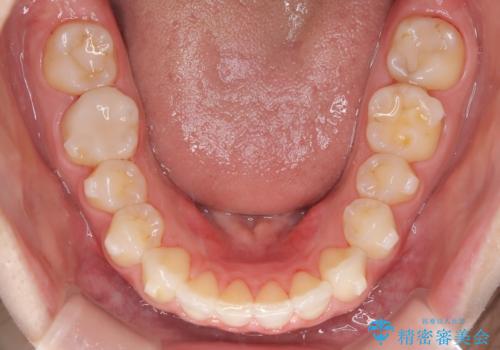

- 治療計画

- 患者様は、上下顎の歯列不正と前歯部の突出感を主訴としてご来院されました。診断の結果、上顎左右第一小臼歯を抜歯することでスペースを確保し、歯列全体を整える方針としました。本来はワイヤー矯正が推奨されるケースですが、患者様のご希望により、透明なマウスピース型矯正装置「インビザライン」を使用した治療計画を立案しました。治療期間は約3年で、奥歯の噛み合わせを維持しながら、徐々に前歯の位置を整えました。

インビザラインは見た目の目立ちにくさと取り外しが可能な点がメリットですが、複雑なケースでは治療計画の精密さが求められます。本症例では奥歯の噛み合わせが崩れないよう注意を払いながら、マウスピースの交換タイミングを細かく設定しました。患者様には装着時間を守っていただくことが重要で、1日20時間以上の装着が必須です。また、抜歯部位のスペースを閉じる過程で、歯の動きが停滞しやすい時期もあるため、定期的なチェックを通じて治療が順調に進むよう管理しました。